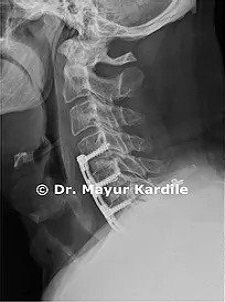

ACDF for Cervical Radiculopathy

61 yr gentleman